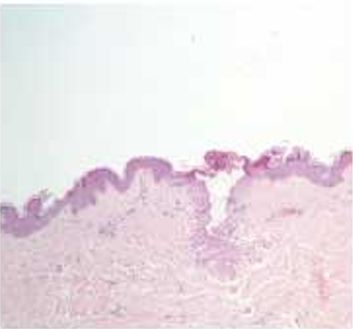

| Гистология |

|